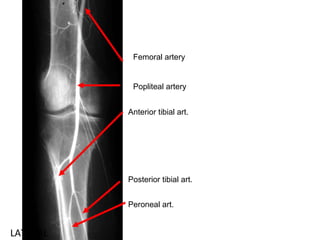

Femoral artery

Popliteal artery

Anterior tibial art.

Posterior tibial art.

Peroneal art.

LATERAL Femoral artery Popliteal artery Anteriortibial art. Posterior tibial art. Peroneal art.